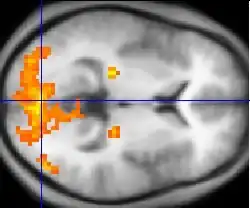

Ressonância magnética funcional

A ressonância magnética funcional (FMRI) e a rotulagem de rotação arterial (ASL) dependem das propriedades paramagnéticas da hemoglobina oxigenada e desoxigenada para ver imagens de alteração do fluxo sanguíneo no cérebro associado à atividade neural. Isso permite a geração de imagens que refletem quais estruturas cerebrais são ativadas (e como) durante o desempenho de diferentes tarefas ou em estado de repouso. De acordo com a hipótese de oxigenação, as mudanças no uso de oxigênio no fluxo sanguíneo cerebral regional durante a atividade cognitiva ou comportamental podem ser associadas aos neurônios regionais como diretamente relacionados às tarefas cognitivas ou comportamentais atendidas.

A maioria dos scanners de FMRI permite que os indivíduos sejam apresentados com diferentes imagens visuais, sons e estímulos de toque, e para fazer diferentes ações, como pressionar um botão ou mover um joystick. Consequentemente, o FMRI pode ser usado para revelar estruturas cerebrais e processos associados à percepção, pensamento e ação. A resolução do FMRI é de aproximadamente 2-3 milímetros no presente, limitada pela disseminação espacial da resposta hemodinâmica à atividade neural. Ele substituiu em grande parte o PET para o estudo dos padrões de ativação cerebral. O PET, no entanto, retém a vantagem significativa de ser capaz de identificar receptores específicos do cérebro (ou transportadores) associados a neurotransmissores específicos através da sua capacidade de imagem de "ligandos" de receptores radiomarcados (os ligandos do receptor são quaisquer produtos químicos que se encaixam nos receptores).

Além da pesquisa em assuntos saudáveis, o FMRI é cada vez mais utilizado para o diagnóstico médico da doença. Como o FMRI é esquisitamente sensível ao uso de oxigênio no fluxo sanguíneo, é extremamente sensível às mudanças iniciais no cérebro resultantes da isquemia (fluxo sanguíneo anormalmente baixo), como as mudanças que se seguem ao AVC. O diagnóstico precoce de certos tipos de acidente vascular cerebral é cada vez mais importante na neurologia, uma vez que as substâncias que dissolvem coágulos sanguíneos podem ser usadas nas primeiras horas após a ocorrência de certos tipos de acidente vascular cerebral, mas são perigosas para uso posterior. As alterações cerebrais observadas no FMRI podem ajudar a tomar a decisão de tratar com esses agentes. Com uma precisão de 72% a 90%, onde a chance alcançaria 0,8%,[15] as técnicas de FMRI podem decidir qual de um conjunto de imagens conhecidas que o sujeito está visualizando.[16]